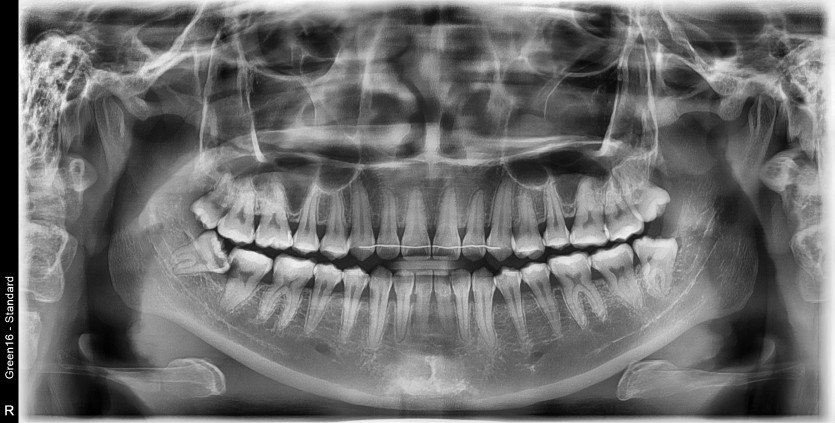

#38 사랑니 발치

구강 외과 전문의가 당일 발치했습니다.